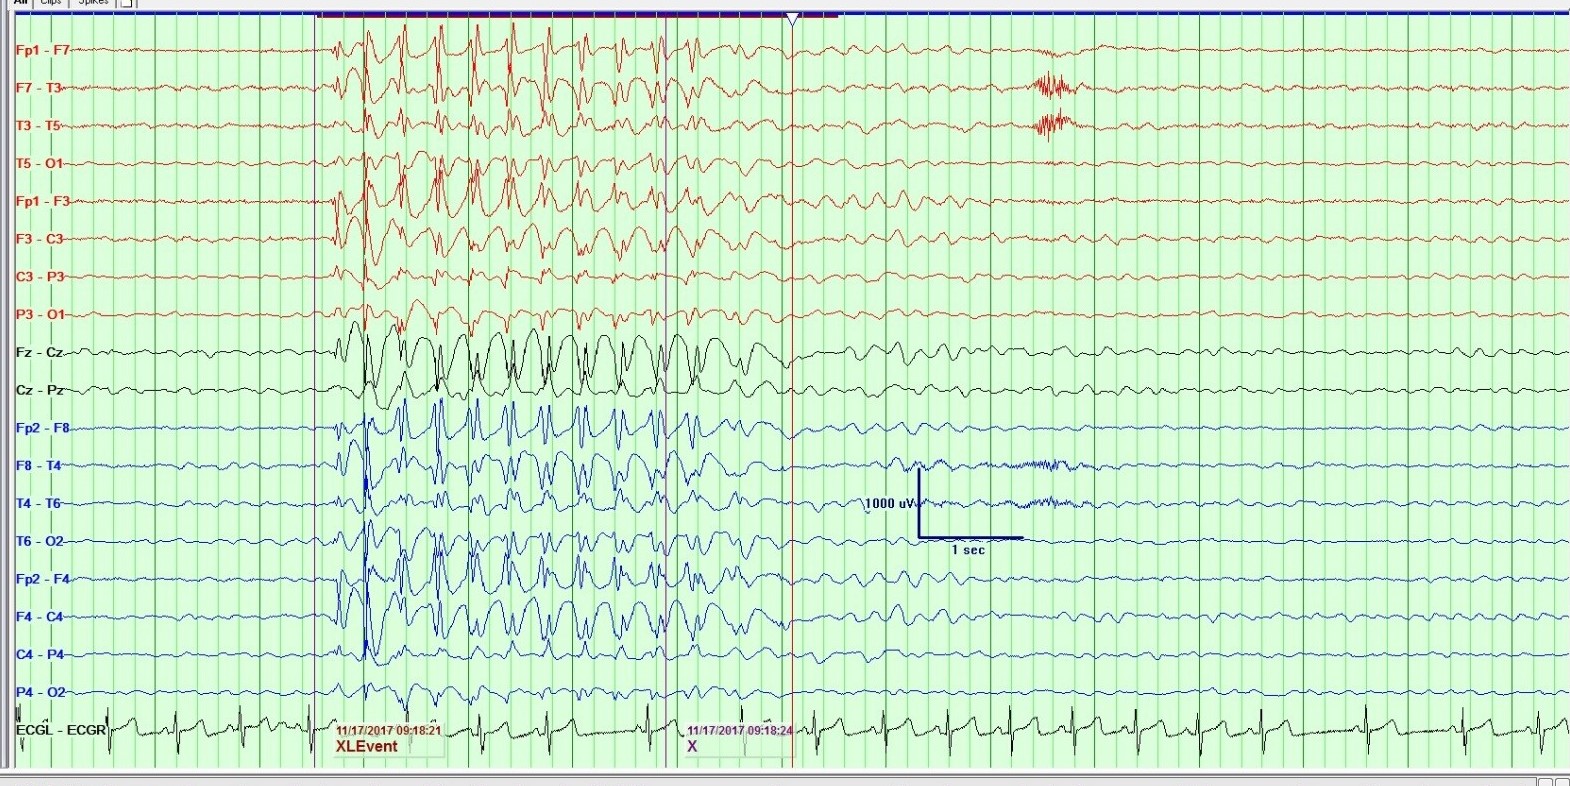

Se realizó EEG con privación de sueño, dónde se mostraban descargas generalizadas de complejos de punta onda a 3 ciclos por segundo que aparecían durante la estimulación luminosa intermitente, durante la hiperventilación, y en vigilia de hasta 7 segundos de duración (Ver figura 1). Durante las descargas se evidenciaba desconexión del medio con mirada fija y, en alguna ocasión, automatismos orales.

Figura 1. Descargas generalizadas de complejos de punta onda a 3 ciclos por segundo.